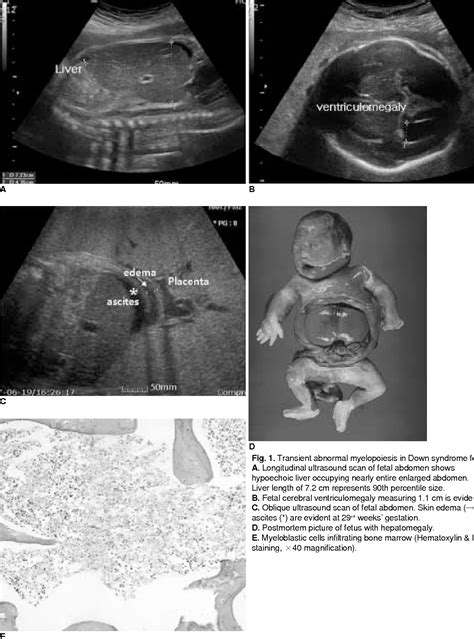

Down syndrome, also known as Trisomy 21, is a genetic condition caused by an extra copy of chromosome 21. While it cannot be diagnosed solely by looking at an image, certain physical features or markers can be identified during routine prenatal scans. When a sonographer or doctor talks about markers for Downs syndrome on ultrasound, they are referring to anatomical characteristics that are statistically more common in fetuses with this condition than in those without it.

During the first and second trimesters, doctors look for specific anatomical findings. The most well-known screening takes place between 11 and 14 weeks of gestation, known as the Nuchal Translucency (NT) scan. Here are some of the markers that clinicians pay close attention to:

• Nuchal Translucency: This refers to the fluid-filled space at the back of the baby's neck. A thickened NT measurement can be an indicator of potential genetic issues.

• Cardiac Abnormalities: Certain heart defects, such as atrioventricular septal defects, are more common in fetuses with Down syndrome.

• Shortened Limb Bones: Sometimes, the humerus (upper arm bone) or femur (thigh bone) may measure slightly shorter than the gestational age suggests.

• Renal Pyelectasis: A slight dilation of the renal pelvis (part of the kidney) can sometimes be noted.